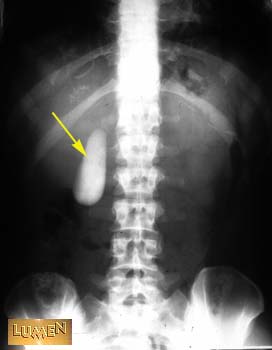

Question: Identify.

Gall bladder.